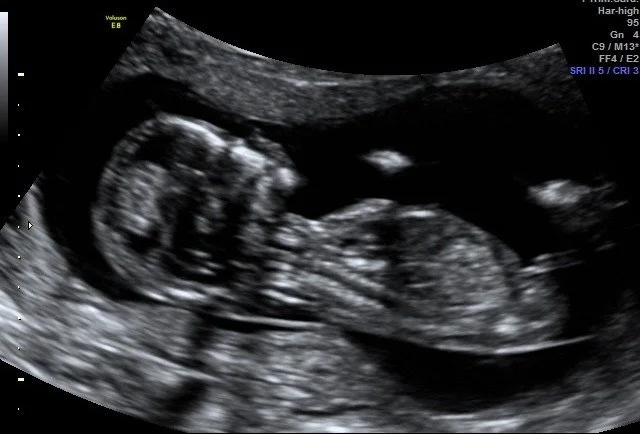

GP Antenatal Shared Care

I enjoy being able to provide pregnancy support. Pregnancy is a deeply transformative time physically and emotionally. I am here to answer all of your questions, which are all legitimate. Pregnancy does come with a lot of side effects!

I am registered as a GP Antenatal Shared Care Provider within Nepean Blue Mountains area which includes maternity services at Nepean Hospital and Blue Mountains Hospital.